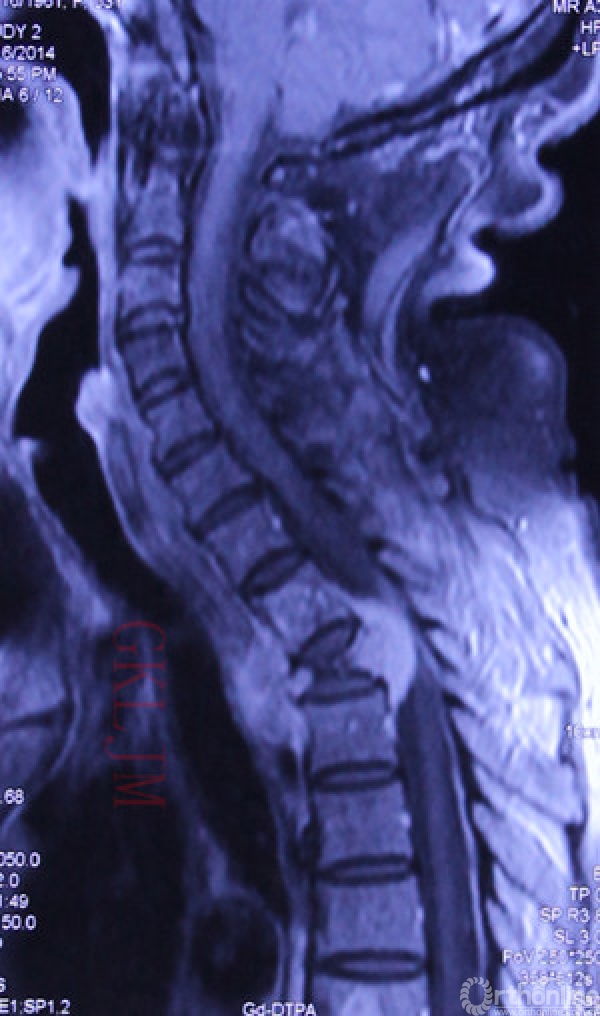

术前MRI示肿瘤侵及T1-3,T2病理骨折,椎旁及椎管内软组织包块形成,脊髓受压